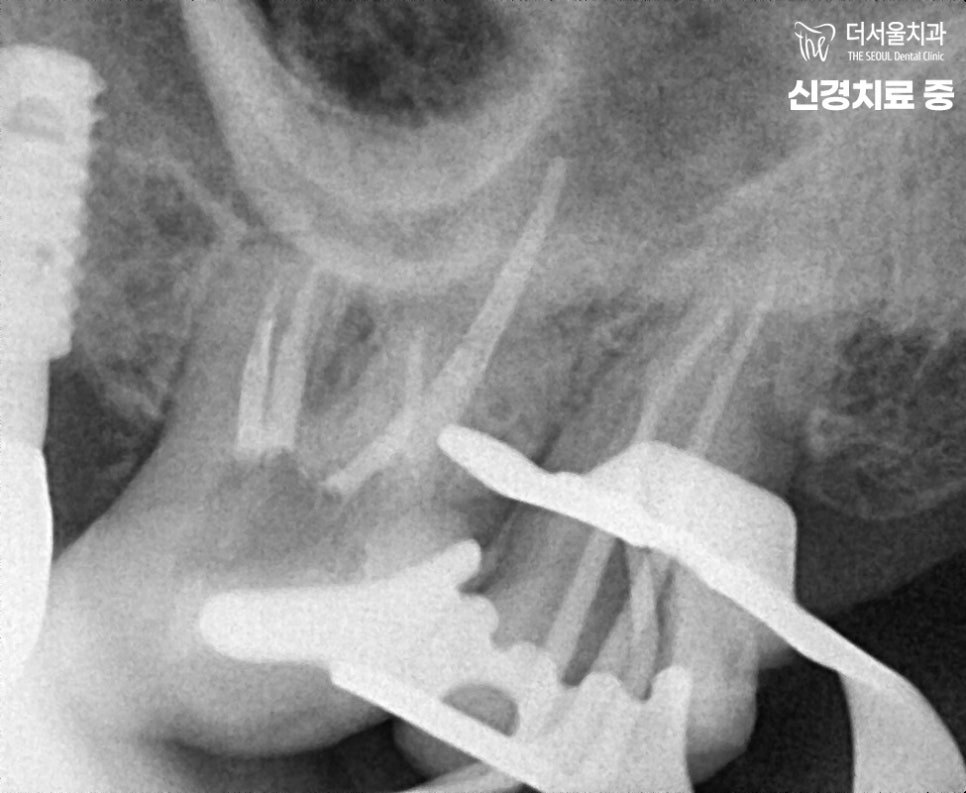

『26, 27 어금니 신경치료 시작』

감염된 조직을 모두 제거 후,

깨끗하게 소독을 여러번 진행하여

재발하는 일이 없도록 해드렸습니다.

이후, GP cone이라는 것을 넣어

빈 근관을 충전해줍니다.